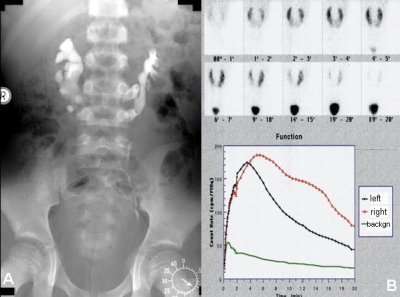

Im Rahmen der Aufnahmeuntersuchung wurde routinemäßig eine Sonographie der Nieren durchgeführt (

s. Männlicher Genitaltrakt/Hoden/Maldeszensus testis). Hier fanden sich beidseits malrotierte Nieren. Bei genauerer Sichtung konnte eine Gewebebrücke zwischen den unteren Nierenpolen gesehen werden - Hufeisenniere. Im i.v.-Pyelogramm ergab sich der Verdacht auf eine geringradige Abflussbehinderung des linken Anteils. Was sich auch im Isotopennephrogramm dokumentierte (Abbildung 3).